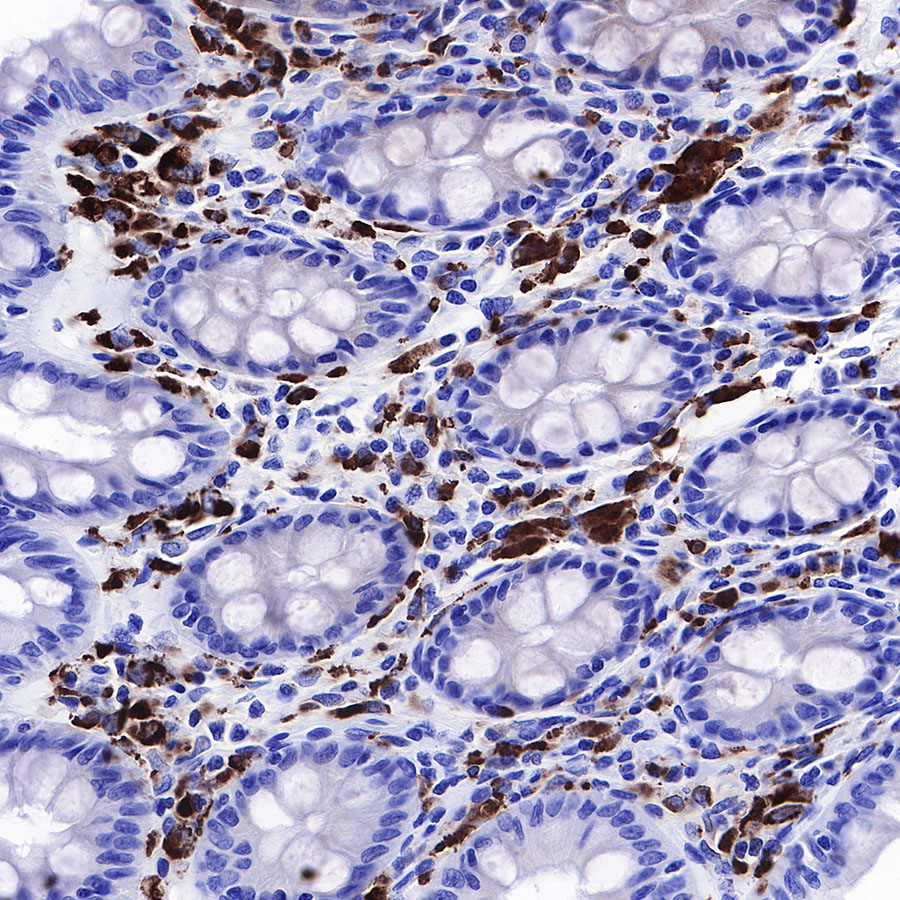

IHC shows positive staining in paraffin-embedded human colon. Anti-CD68 antibody was used at 1/1000 dilution, followed by a HRP Polymer for Mouse & Rabbit IgG (ready to use). Counterstained with hematoxylin. Heat mediated antigen retrieval with Tris/EDTA buffer pH9.0 was performed before commencing with IHC staining protocol.